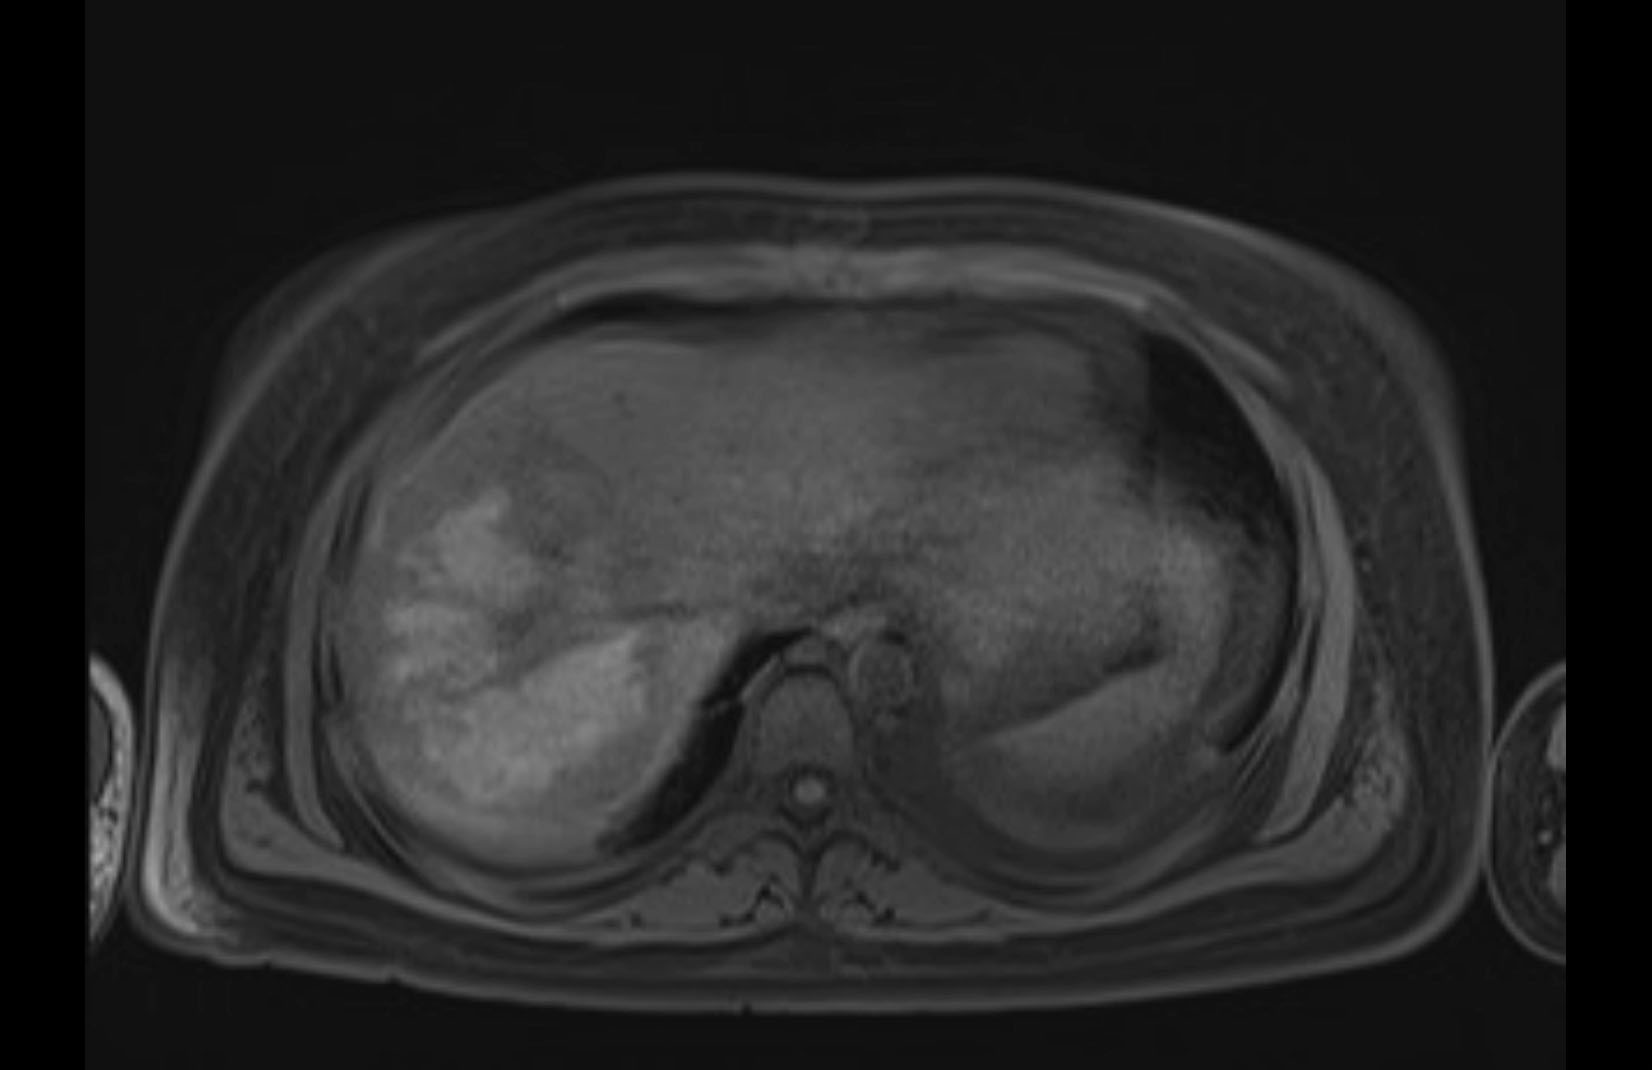

Imaging Analysis

Look through the patient's CT scan to identify any areas of concern for the necessary procedure.

MRI T1

Based on initial findings, which issue(s) would you be most concerned about?